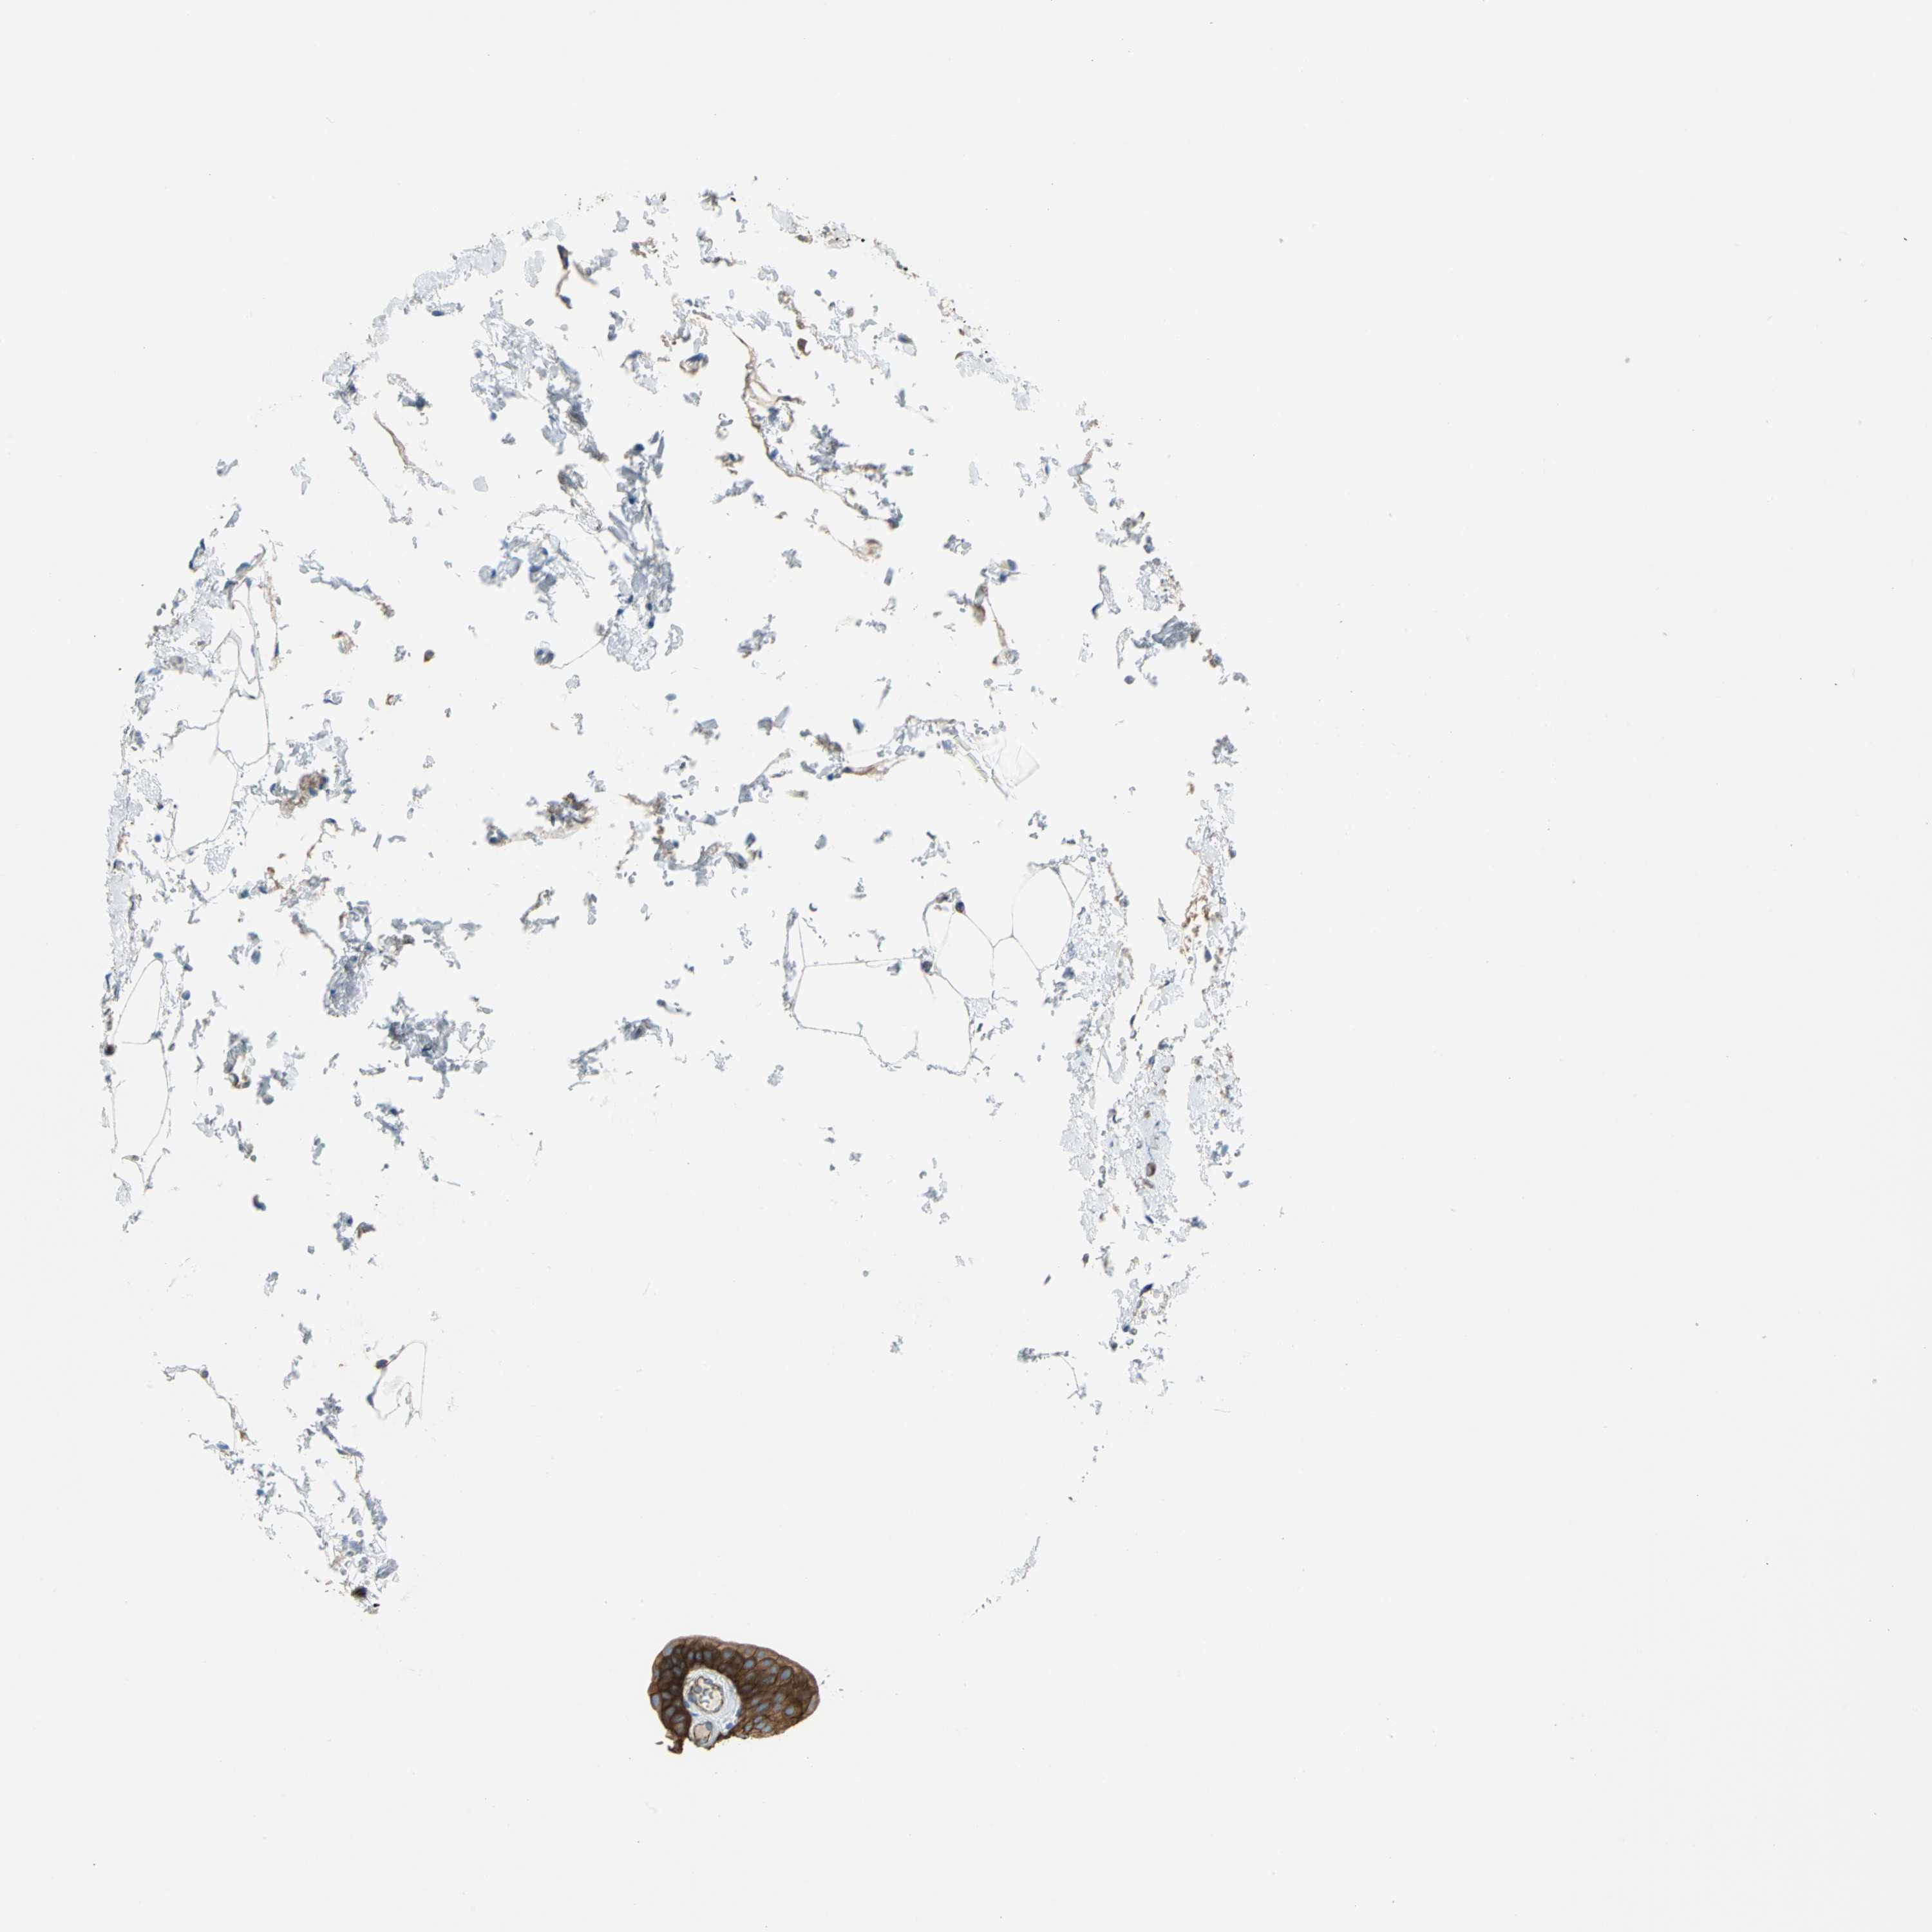

UROTHELIAL CANCER - Protein expressioni

A mouse-over function shows sample information and annotation data. Click on an image to view it in a full screen mode. Samples can be filtered based on level of antibody staining by selecting one or several of the following categories: high, medium, low and not detected. The assay and annotation is described here.

Note that samples used for immunohistochemistry by the Human Protein Atlas do not correspond to samples in the TCGA dataset.

Antibody stainingi

Antibody staining in the annotated cell types in the current human tissue is reported as not detected, low, medium, or high, based on conventional immunohistochemistry profiling in selected tissues. This score is based on the combination of the staining intensity and fraction of stained cells.

Each image is clickable and will lead to virtual microscopy that enables deeper exploration of all samples and also displays staining intensity scores, fraction scores and subcellular localization as well as patient and tissue information for each sample.

Antibody HPA004747

Antibody HPA004886

Antibody CAB019322

Staining

High

Medium

Low

Not detected

Intensity

Strong

Moderate

Weak

Negative

Quantity

>75%

75%-25%

<25%

None

Location

Nuclear

Cytoplasmic/membranous

Cytoplasmic/membranous,nuclear

Urothelial carcinoma, High grade

Urothelial carcinoma, Low grade